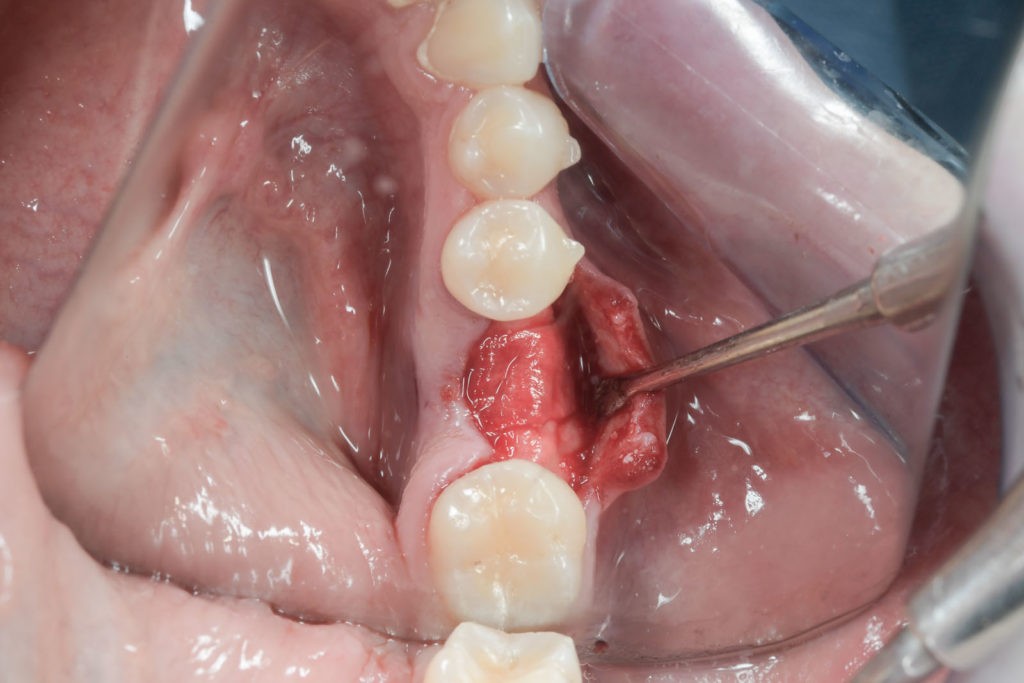

• Użycie drobin kości własnej do pokrycia ubytków na niewielkim obszarze, jak obnażenia gwintu implantu podczas implantacji, obnażenie korzeni zęba czy furkacji korzeniowych. Wiórki kostne pobierane są podczas zabiegu specjalnymi aplikatorami (skrobaczkami) z powierzchni kości szczęk i żuchwy.

Zabieg odbudowy zębodołu powinno się wykonać możliwe jak najszybciej po usunięciu zęba. Jego celem jest odbudowa naturalnej objętości kości w miejscu utraconego zęba, a następnie szybkie wprowadzenie implantu. Najlepsze rezultaty uzyskuje się przy zastosowaniu biomateriału w formie bloczków kolagenowych lub granulatu, które dają trwałe efekty odbudowy oraz optymalną funkcję i estetykę odtworzonych koron zębów na wszczepionym implancie.

Procedury te są stosowane w sytuacji niedostatecznej ilości kości, skutkującej odsłonięciem gwintu, podczas gdy wszczepiamy implanty stomatologiczne lub też jako zabiegi poprzedzające ich wprowadzenie.​